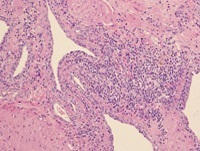

Cytologisch beeld van BPH van een zuigbiopt (links) en een percutaan biopt